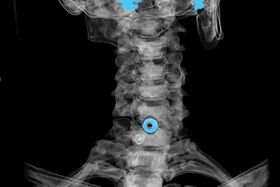

The diagnosis is established on the basis of characteristic symptoms, as well as using:

- X-rays.The method is ineffective, especially in the last stages of osteochondrosis development.

- MRI (magnetic resonance imaging) of the cervical spine.A method that allows you to see bone structures, herniated intervertebral discs, their size and direction of development.

- Computed tomography.A less effective solution than MRI, since the presence and size of hernias is difficult to determine.